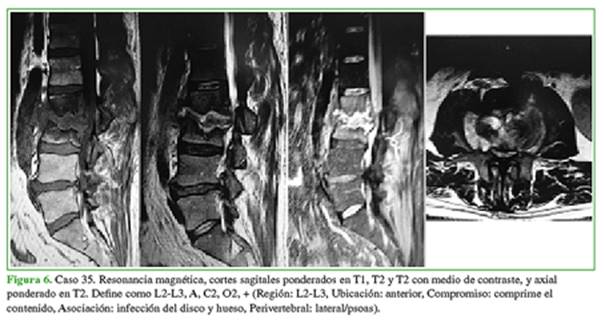

El coeficiente kappa de Cohen sobre el acuerdo intra- e interobservador global fue de 0,76, lo que se considera una muy buena concordancia de reproducibilidad. Los valores de cada parámetro en particular fueron: R 0,94; U 0,88; C 0,55, según la ventana de la resonancia y el uso de medio de contraste; A 0,67 y P 0,77. Los tres primeros parámetros dan una noción de volumen que, en un próximo proceso, se podría relacionar con la toma de una decisión terapéutica y los dos últimos indican la presencia de focos infecciosos vertebrales por fuera del conducto (Figuras 4-6).

La ventana ponderada en T2 con gadolinio fue la imagen con mayor acuerdo entre los evaluadores (kappa >0,87) en todos los cortes, seguida de la T2 sin contraste, STIR y, por último, T1 sin contraste.